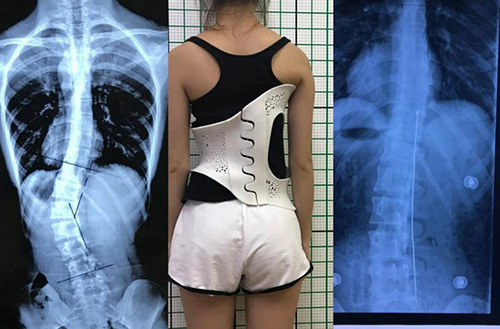

3D打印技術(shù)在骨科的實(shí)際應(yīng)用有哪些?(圖4)

(3D掃描和3D打印技術(shù)輔助制造的個(gè)性化脊柱矯正支具)